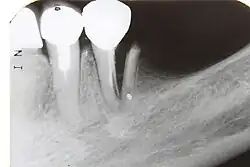

Radiographic signs of periapical inflammation is usually evident in a tooth with necrotic pulp

Root resorption